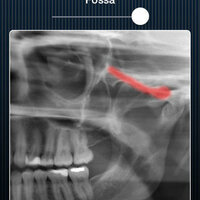

Dental Panoramic Radiology is an interactive application designed to teach panoramic anatomy. It is intended to be a self-instructional module that can be used by students to prepare for exams or clinic, and by dental professionals as a convenient and practical review tool. Anatomical landmarks within the maxilla, mandible, and surrounding structures are labeled on panoramic radiographs and a three dimensional view is provided for correlation. A description of the principles of panoramic imaging and a brief explanation for all labeled anatomical structures are also included in this module.